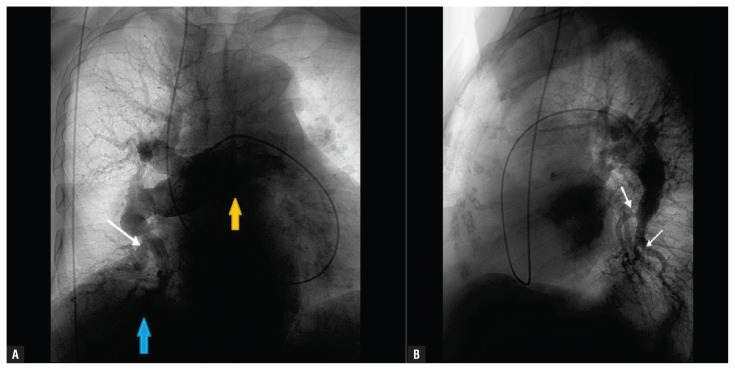

Abstract Image